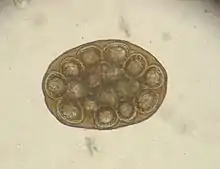

- Dipylidium caninum egg packet